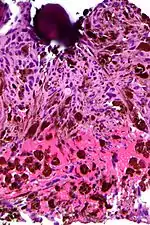

Micrograph of a psammomatous melanotic schwannoma with a psammoma body, as may be seen in Carney complex. H&E stain.

A psammoma body is a round collection of calcium, seen microscopically. The term is derived from the Greek word ψάμμος (psámmos), meaning "sand".

Psammoma bodies usually have a laminar appearance, are circular, acellular and basophilic.